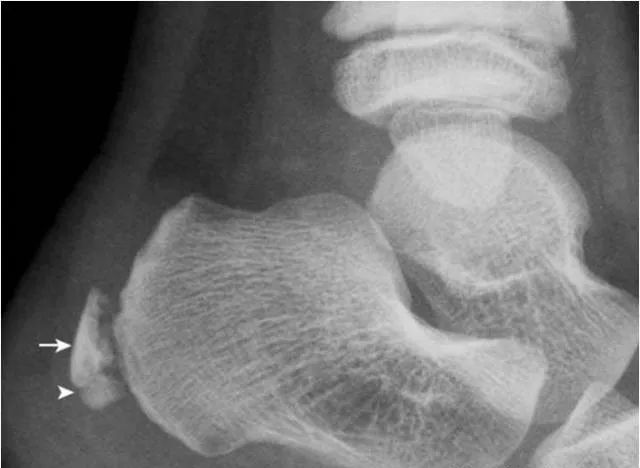

1.跟骨结节骨骺:

形态多样,密度致密(箭),伴裂隙(箭头),为正常表现,勿误认为坏死。